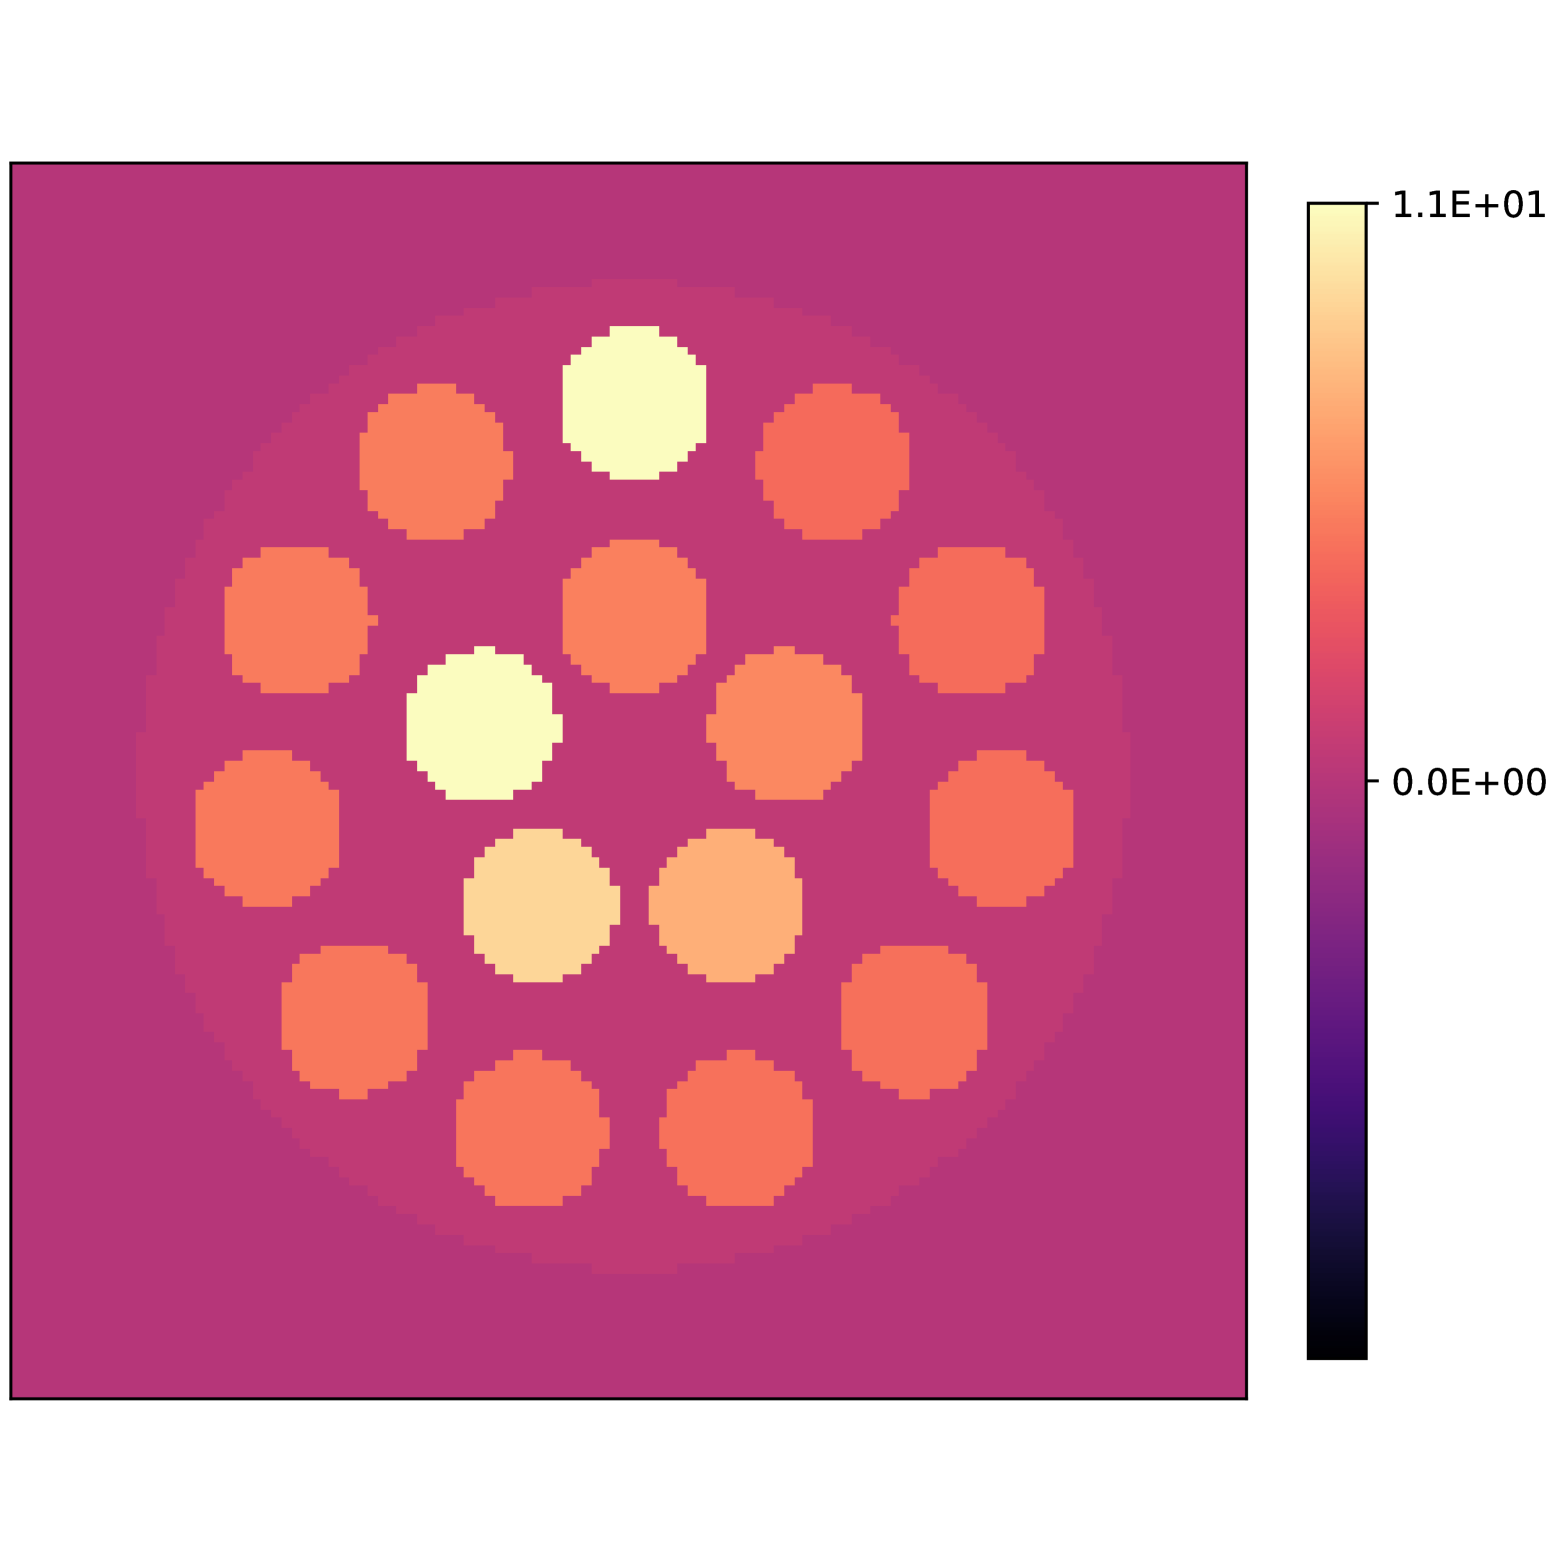

Our theoretical results show that generic concentrations and maps can be recovered exactly even when the fieldmap is not identifiable. To illustrate the impact of this fact, we perform a recovery experiment on a water (Fig. 2(a)), fat (Fig. 2(b)) and silicone (Fig. 2(c)) in silico phantom. The concentrations are all real. The values for the fieldmap and used to generate the signal are shown in Figs. 2(d) and 2(e). The echo times have the form where ms and ms with .

We solve (23) using projected gradient descent as initial iterate a vector with all components equal to one. Forward finite-differences were used to compute the gradient. The bound on the norm of the gradient is Hz at voxels with non-zero signal magnitude, and kHz at voxels with zero signal magnitude. This avoids imposing artificial constraints at voxels with no signal. The step size used is and the termination conditions

In Figs. 2(f), 2(g) and 2(h) show the recovered concentrations of water, fat and silicone, and Fig. 2(j) shows the recovered . These recovered quantities are all qualitatively similar to their true values. In contrast, Fig. 2(i) shows the recovered fieldmap, which differs from its true value. By comparing the errors in the recovered concentrations, we see that they are within a reasonable accuracy except in regions with a large magnitude for the fieldmap gradient, indicating a bound that is too small (Figs. 2(k), 2(l) and 2(m)). A similar behavior is seen in the recovered (Fig. 2(o)). The error for the recovered fieldmap tends to be larger outside the area of the phantom (Fig. 2(n)).